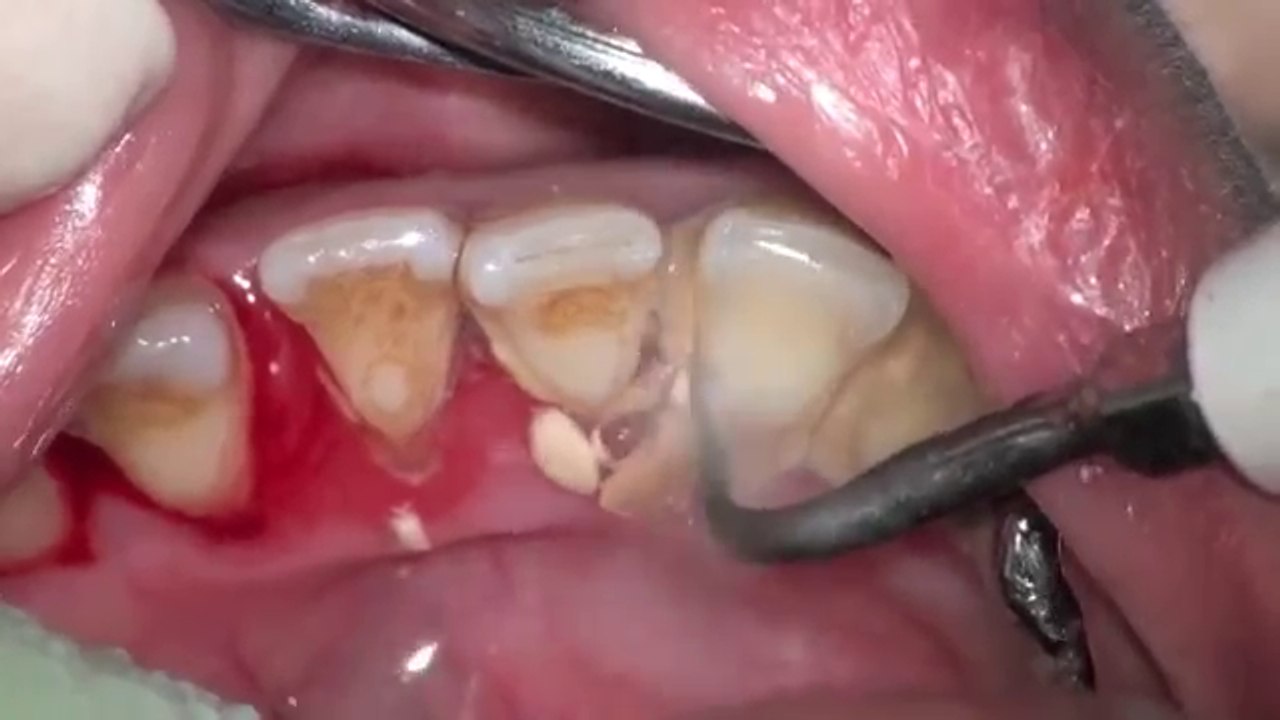

mais il se peut que ces caries, deja existantes sous la plaque, soient maintenant mises en evidence. La dentisterie cosmétique et restauratrice moderne offre plusieurs solutions efficaces pour corriger ou minimiser l'apparence des triangles noirs entre les dents.

Source: methodisypl.pages.dev Dentaire Docteur Idriss Cherkaoui, Rabat La carie dentaire , Des sensibilités invalidantes, notamment au froid et au chaud, des aliments coincés entre les dents, dans les espaces élargis par la rétraction des gencives, un effet esthétique malheureux en raison des espaces sombres entre les dents (les trous noirs) qui vieillissent les personnes d'autant plus que la coloration plus sombre de la. mais il se peut que ces caries, deja.

Source: englesongoa.pages.dev La parodontologie Clinique Dentaire Nifa , L'orthodontie est une des possibilités, examinons tout cela ensemble mais il se peut que ces caries, deja existantes sous la plaque, soient maintenant mises en evidence.